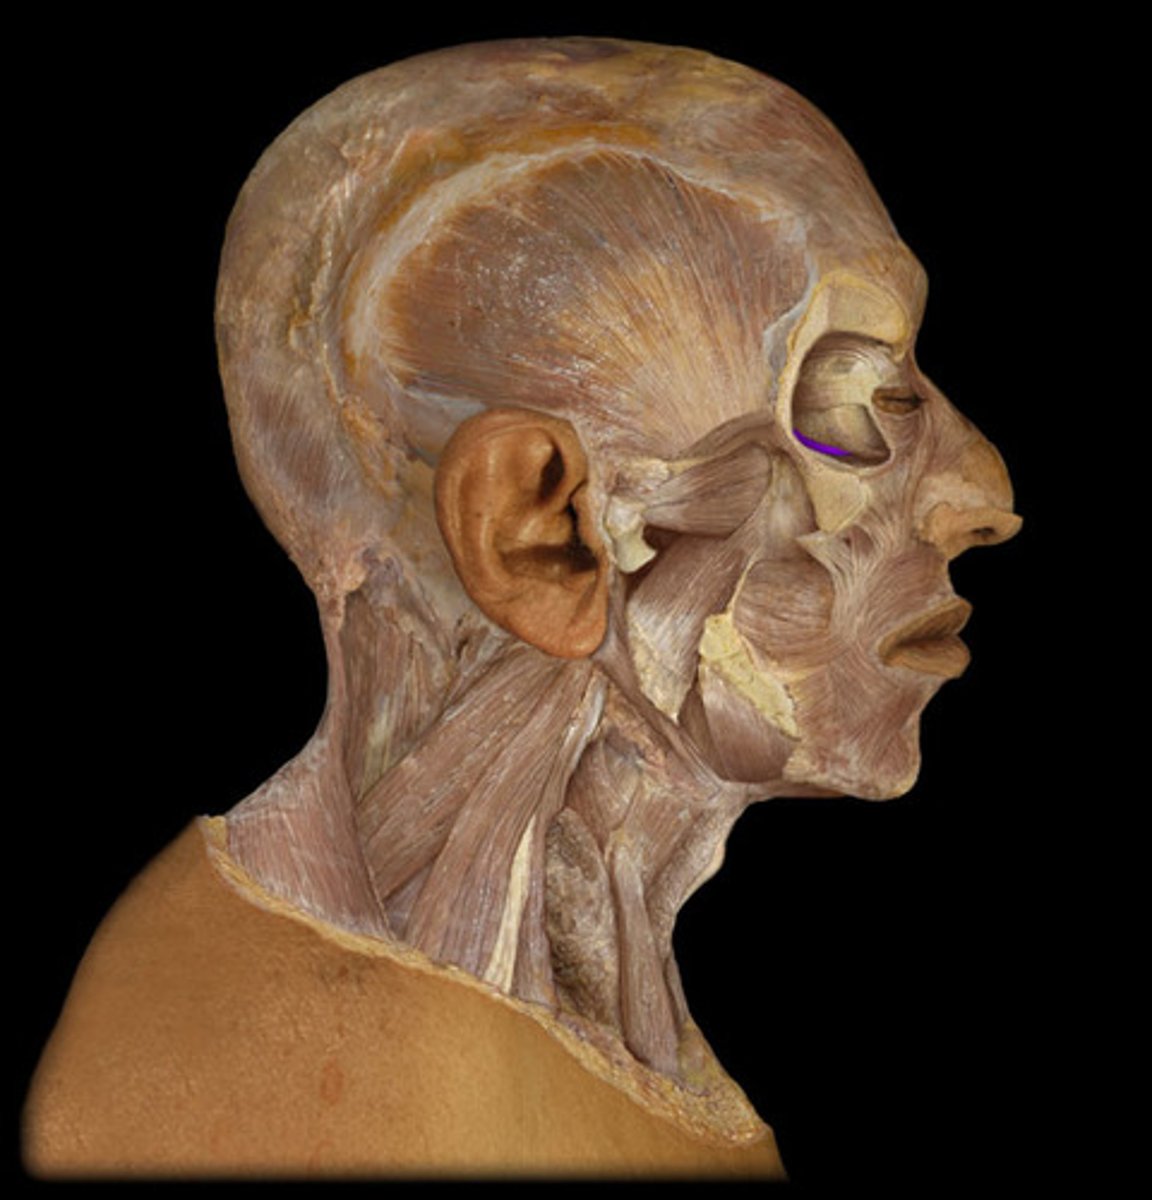

Orbicularis oculi

Levator palpebrae superioris